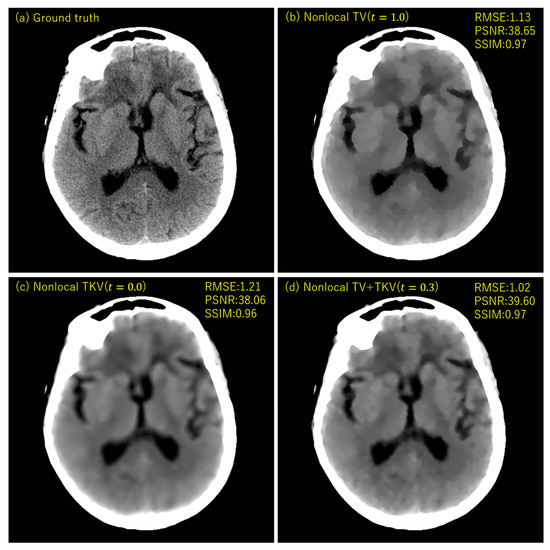

3. Experimental Results

4. Discussion

| Nonlocal TV | Nonlocal TKV | Nonlocal TV + TKV | |

| Convergence | Good | Not bad | Good |

| High contrast | Yes | No | Yes |

| Smooth intensity change | No | Yes | Yes |